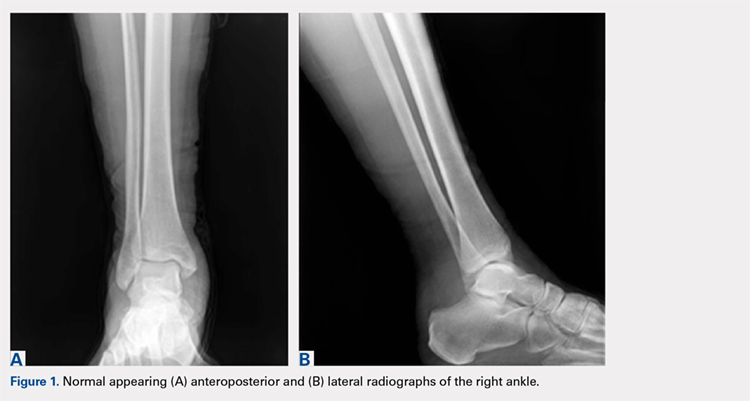

Review of her plain radiographs demonstrated no bony abnormalities, fractures, nor visible deformity (Figures 1A, 1B).